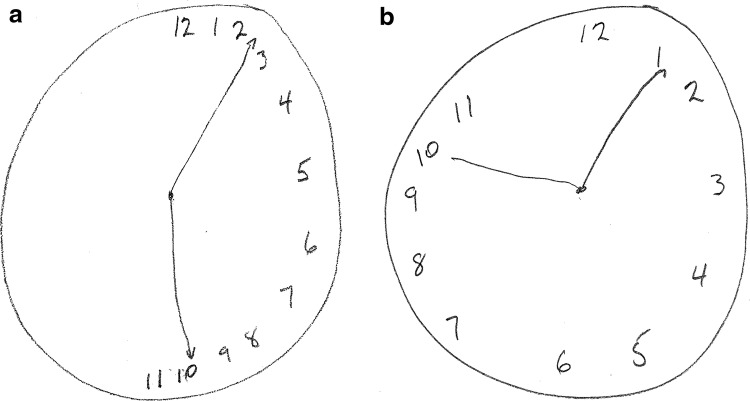

Neglect as a consequence of right brain damage has been recognized at least since J. Hughlings Jackson’s 1876 case report [1]. It was later appreciated that impairment in brain functional connectivity and resulting brain network dysfunction (‘connectopathy’, ‘disconnection syndrome’) underlies hemispatial neglect, a common sequela of right hemispheric stroke [2, 3]. A variety of bedside tests have been found useful as a measure of hemispatial neglect, including the Clock-Drawing Test [4]. The signature pattern of hemispatial neglect seen after right brain damage with the Clock-Drawing Test is a clock face, drawn from memory, lacking numerals in its left half, which has been termed neglect of the left hemispace [5] (Fig. 1a).

Fig. 1.

Clock-drawing test a immediately before perispinal etanercept, and b 30 min after perispinal etanercept

Immediately prior to treatment, examination revealed a left hemiparesis, left-sided spasticity, left sensory loss involving both the left upper and lower extremities, cold allodynia on the left upper extremity, cognitive dysfunction (Montreal Cognitive Assessment score = 19/30), Fatigue Assessment Scale Score [20] of 24/50, and chronic left-sided pain (central post-stroke pain) assessed by the patient as 5/10 in severity on a 0–10 scale. Walking 20 meters took 58 s. The Five Times Sit-to-Stand test required 27 s to complete with assist from his right arm. There was prominent left hemispatial neglect, as measured by the Clock-Drawing Test (Fig. 1a). As standard procedure in our medical practice, a Clock-Drawing Test is administered immediately before and within 30 min after treatment. As part of the Clock-Drawing Test, the patient is verbally instructed to ‘draw a big round clock, with all of the numbers on it’. After the clock has been drawn, the patient is then verbally instructed to ‘make the clock say 10 past 11’.

After informed consent was obtained, etanercept 25 mg was administered by perispinal injection, followed by Trendelenburg positioning, as previously described [10]. Within 10 min, the patient reported that his chronic left-sided post-stroke pain was gone. Within 30 min after etanercept administration, the patient reported a complete absence of his chronic left-sided pain, a reduction in spasticity, and improvements in gait, balance, the ability to turn to the left, and the ability to perceive the position of his left foot. A repeat Clock-Drawing Test performed 30 min after perispinal etanercept injection no longer showed left hemispatial neglect (Fig. 1b). Seventeen days after treatment, the patient reported, by telephone, his neurological improvements had been maintained, with complete absence of pain, absence of allodynia, and improved peripheral vision. His report of reduced fatigue was supported by his Fatigue Assessment Score, which remained reduced by 7 points, measured as 17/50, at both 1 and 2 months after treatment. Eleven months after receiving his single 25 mg dose of perispinal etanercept, the patient reported sustained neurological improvement, when reached by telephone. He specifically reported that his previously chronic and intractable post-stroke pain that had immediately resolved after receiving perispinal etanercept had never returned. A movie file documents this patient’s clinical response to perispinal etanercept treatment in more detail (see Online Resource 1, video before and after perispinal etanercept, 16 years after stroke).

Evidence that perispinal etanercept had the potential to improve chronic brain dysfunction was first published in 2006 [15]. The first report of rapid improvement in chronic post-stroke neurological dysfunction following perispinal etanercept was published in 2011 [7]. A 2012 observational study involving 617 patients treated with perispinal etanercept for chronic post-stroke neurological dysfunction included mention of a single patient with improvement in hemispatial neglect, beginning 2 h after perispinal etanercept was administered, but changes in clock drawing were not reported [8]. This is the first report and documentation of immediate improvement in hemispatial neglect, as measured by the Clock-Drawing Test, in a patient with chronic, intractable hemispatial neglect following perispinal etanercept administration.

Improvement in cognitive function within minutes after perispinal etanercept in patients with Alzheimer’s disease was the initial clinical evidence suggesting the rapid synaptic and brain network effects of perispinal etanercept [6]. Subsequently, rapid improvement in neurological function after perispinal etanercept was reported in patients with multiple additional chronic brain disorders [6–10, 14, 16]. Rapid improvement in neglect of the left hemispace in the Clock-Drawing Test after perispinal etanercept is consistent with these previous clinical observations; the growing body of evidence documenting the existence of chronic brain inflammation after stroke and traumatic brain injury; independent evidence that neuroinflammation is associated with a reduction in functional connectivity in the brain; the rapid synaptic and neuronal effects produced by TNF in animal studies; and improvement in stroke outcomes after receiving etanercept in multiple animal models [6–12, 14, 16, 21–24]. Rapid improvement of hemispatial neglect after perispinal etanercept is also consistent with the concept that hemispatial neglect reflects brain network dysfunction and a disturbance in functional connectivity that is mediated by TNF.

the replication of the same distinctive pattern of improvement in clock drawing (immediate resolution of neglect of the left hemispace) in multiple post-stroke patients;

The striking pattern of immediate improvement in clock drawing documented in this patient with chronic, previously intractable, central post-stroke pain, chronic post-stroke fatigue, and left hemispatial neglect is most consistent with rapid restoration of brain functional connectivity. This evidence suggests hemispatial neglect may be caused by TNF-mediated network dysfunction and impairment in functional connectivity that remains reversible, even years after stroke. This evidence also suggests that central post-stroke pain may be mediated by TNF.